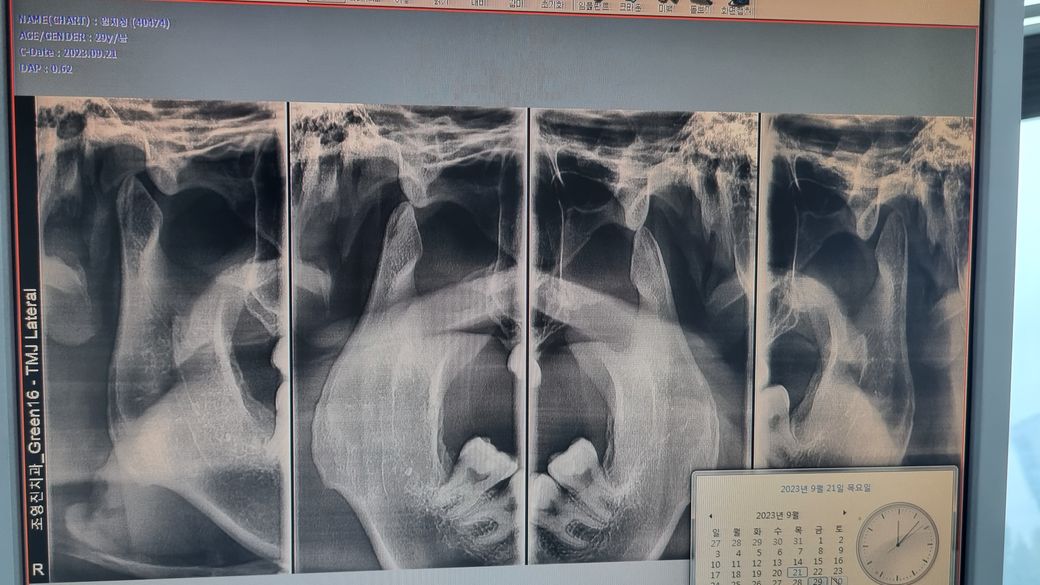

턱관절 마모가 심해서 스프린트 해야 할 정도인가요?

해당사진은 턱관절 파노라마 사진입니다.

방사선 사진을 통해 보기로는 턱관절의 osteophyte(골성융기)가 의심됩니다. 뼈에 과도한 힘이나 염증 자극에 의해 뼈 모양이 칼날 모양으로 변형되는 것입니다.

정상적인 아래턱관절 뼈 모양은 엄지손가락을 쭉 펼친 모양과 비슷합니다.